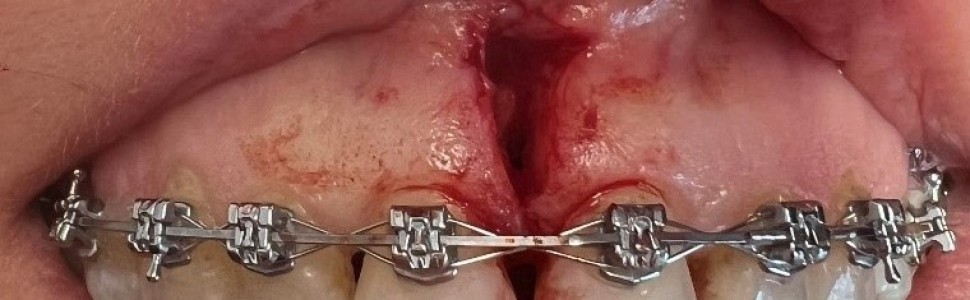

Ryc. 3. Wycięcie wędzidełka wargi skalpelem A. bezpośrednio po wycięciu; B po założeniu szwów.